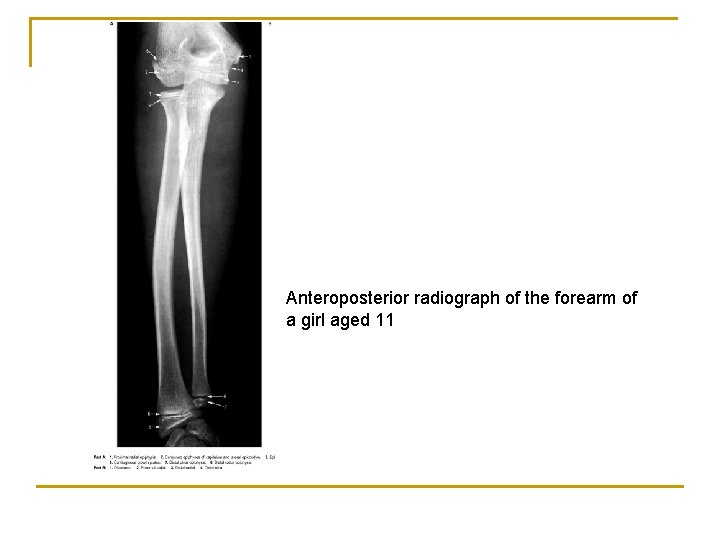

Anteroposterior radiograph of the forearm of a girl aged 11

Colles’ fracture n n Normally, the radial styloid process projects further distally than the ulnar styloid process. Consequently, when fracture within the distal 2 cm of the radius (Colles’ fracture) occurs, this relationship is reversed because of shortening of the radius.